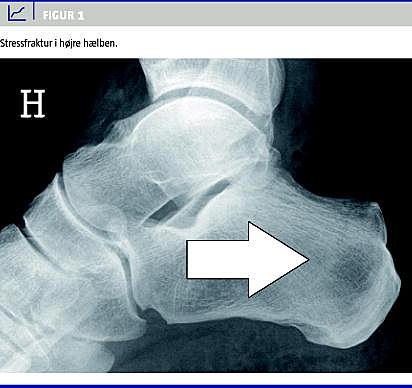

En 51-årig mand fik under løb akutte smerter i højre hæl. Grundet beskedne kliniske tegn afstod skadestuelægen initialt fra røntgen. Ved andet skadestuebesøg efter to uger sås diskret hævelse og ømhed, men på røntgen af hælbenet konstateredes ikke brud (Figur 1 ), og behandlingen var råd om smertestillende medicin.

En gennemgang af røntgenbilledet fra det oprindelige skadestuebesøg (Figur 1) afslørede, at patientens langvarige smerter fra højre hæl skyldtes et ubehandlet overset hælbensbrud. Et år efter debut har patienten aftagende lette smerter i begge hæle og har genoptaget sit arbejde.